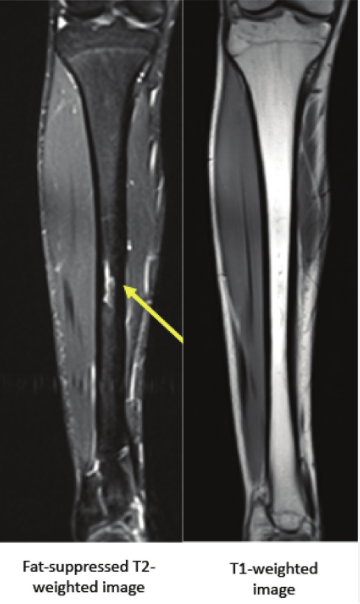

An MRI showing a fracture line in the tibia

• Characteristics: Stress fractures present as acute pain that is localized to the site of the fracture. The pain persists even during rest and may be associated with swelling, bruising, and tenderness to touch. Stress fractures can often be diagnosed through imaging, such as X-rays, bone scans, or MRI, depending on the location and severity.

• Biomechanics: By this stage, the bone has a visible fracture line or crack, which can range from small micro-fractures to more severe breaks that require medical intervention. In runners, stress fractures are most commonly seen in the tibia, metatarsals, femoral neck, and navicular bone.